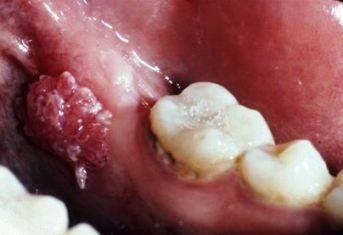

Shown here are condylomata acuminata, associated with human papillomavirus (HPV)-8 and HPV-11; occasionally, infection is caused by HPV-16 and HPV-18. The lesions are usually non-painful and may be solitary or multiple. Lesion color varies from pink to pink-white to white.

Top photo courtesy of Drs Michael Martin and Dolphine Oda; bottom photo courtesy of Dr Tom H. Morton Jr.